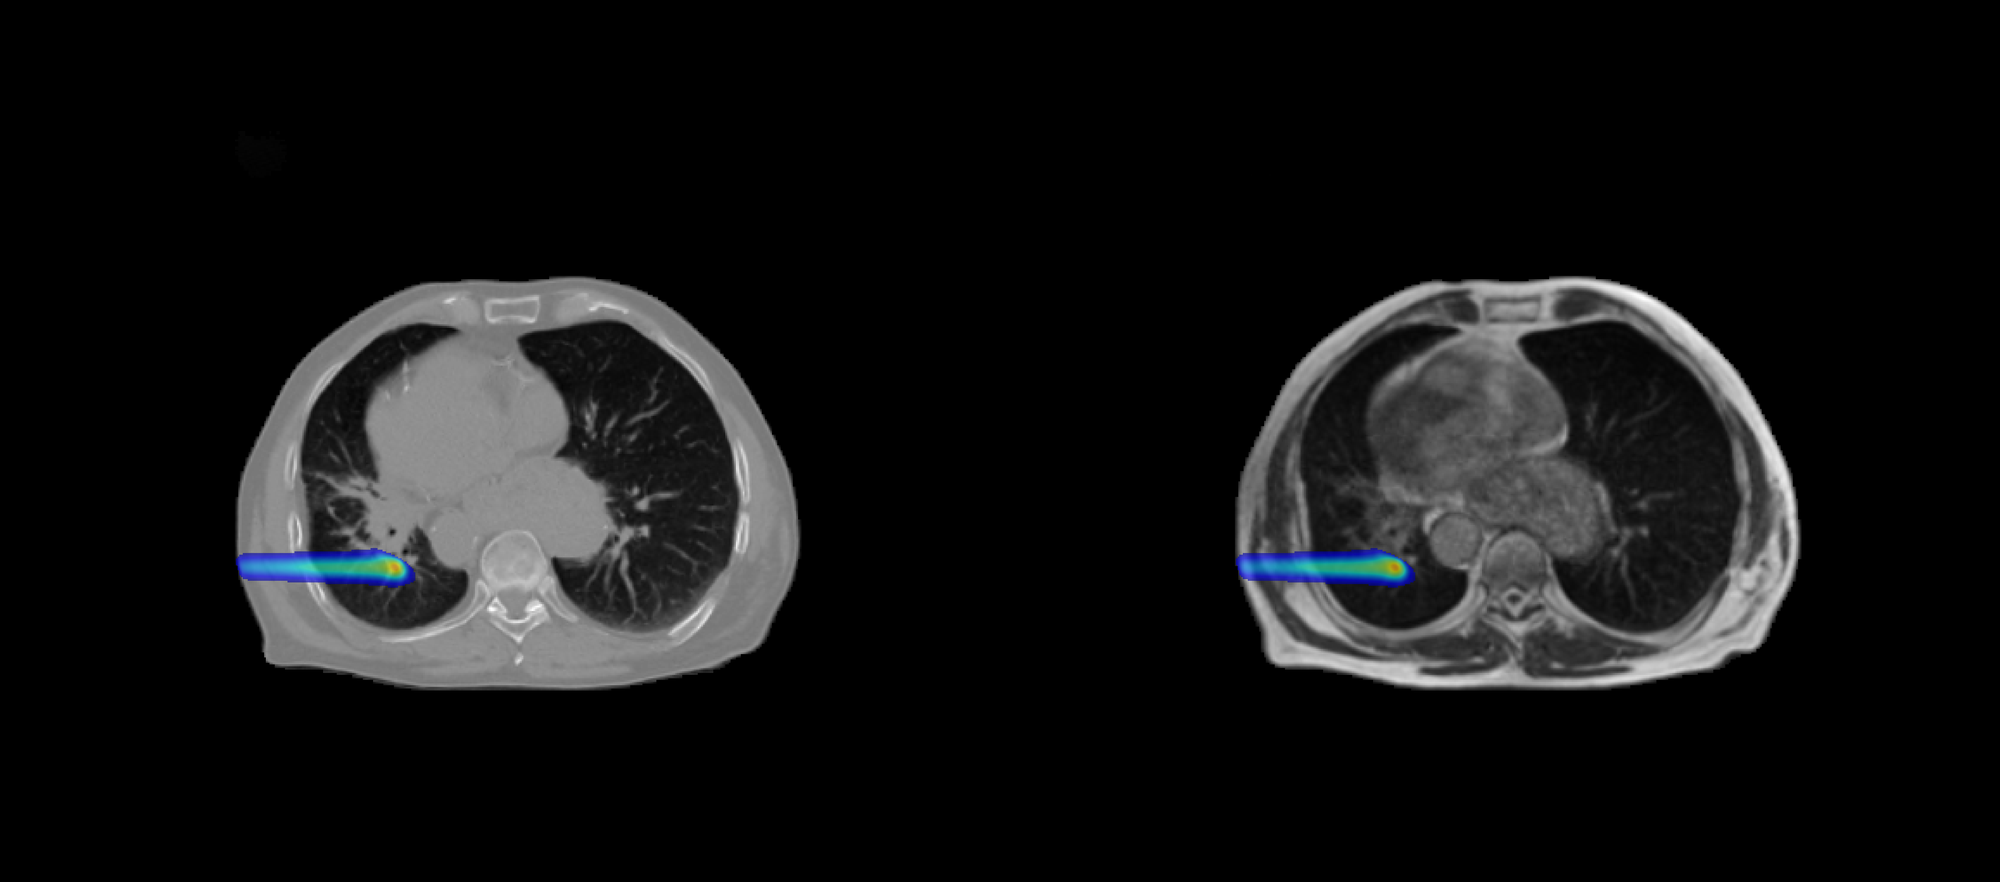

DoseRAD2026 aims to benchmark state-of-the-art methods for fast and accurate radiation dose calculation, for both photon and proton radiotherapy, using either computed tomography (CT) or MRI as input.

The challenge consists of four tasks reflecting current and emerging radiotherapy technologies:

-

Photon dose calculation on CT

Relevant for intensity-modulated photon therapy using volumetric modulated arc therapy (VMAT), the standard treatment modality for the majority of patients. -

Photon dose calculation on MRI

Supporting MRI-guided radiotherapy systems (MRI-linacs), which enable online adaptive treatment based on high soft-tissue contrast imaging.